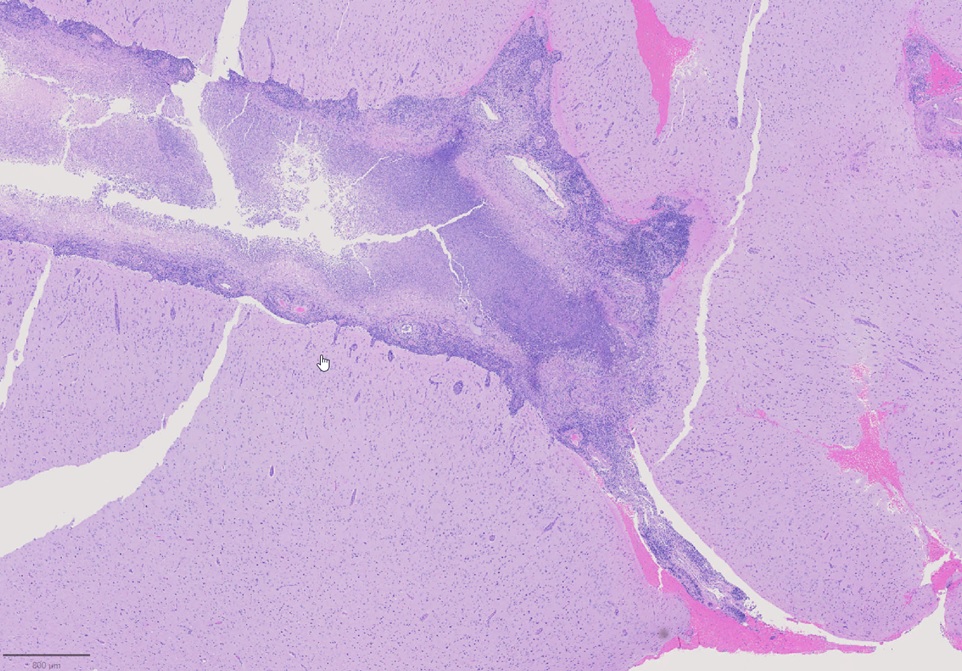

A 79-year-old right handed woman presented to a local hospital with left hemiparesis affecting her upper and lower extremities with mild left facial weakness for the last 2 weeks. She had a longstanding history of RA and had been off immune suppressant therapy for a few months due to improvement in symptoms. She had previously been on methotrexate and adalimumab in the past. She was evaluated with imaging and lumbar puncture (LP) at the time. MRI brain showed a semi-enhancing lesion over the right frontal lobe near the motor cortex with meningeal enhancement (Figure 1). CSF studies showed elevated protein at 65 and pleocytosis with WBC count of 47, 80% lymphocytes. CSF infectious panel was negative, but serum HSV-1 was positive. She reported a cold sore around this time as well. She was treated with broad spectrum antibiotics and acyclovir for 2 weeks. Infectious workup was otherwise negative. She did not have much improvement in her symptoms and was presented to our hospital 3 weeks later. Repeat CSF evaluation showed protein of 70 along with pleocytosis of 33 white blood cell (WBC), 75% lymphocytes. She received treatment with extended broad-spectrum antibiotics for 2 weeks. Rheumatological evaluation was negative for other signs of active RA. EEG showed bitemporal slowing with some quasi-periodic activity over the right temporal regions. She had some left arm shaking as well and was placed on levetiracetam for seizure prophylaxis. She did not have much improvement in her symptoms. A brain biopsy was performed which showed histopathological findings consistent with granulomatous inflammation confirming a diagnosis of RM (Figures 2-4). Labs showed highly elevated rheumatoid factor (RF) (>320) and anti-cyclinolytic citrullinated peptide (CCP) antibodies (>250). Rheumatology was consulted again and recommended high dose therapy with intravenous methylprednisolone for 5 days followed by resumption of immune modulating therapy. She developed a small right frontal ischemic stroke as a resultant of vasculitis from RM which caused exacerbation of left lower extremity weakness (Figure 5). She is kept on aspirin 81 mg daily for maintenance therapy for stroke prevention and levetiracetam for seizure prophylaxis along with daily prednisone and rituximab maintenance therapy for management of her RA / RM from rheumatology. She continues to work with physical therapy for her left hemiparesis which has shown some improvement. She sees rheumatology and neurology for continued follow up.

Figure 2. Leptomeningeal inflammation and necrosis.

Histopathological findings eventually determine the diagnosis. In Bathon's assessment, 17 out of 19 victims had RM diagnosed after postmortem. An open brain biopsy was used to make the diagnosis in two cases. Meninges that had swollen nodules or plaques were frequently seen during a physical examination. Rheumatoid nodules, generalized meningeal inflammation, and vasculitis were three aberrant patterns that emerged through microscopic pathological analysis. The majority of the findings (68%) were nodules, which shared histological similarities with subcutaneous rheumatoid nodules. Nodules were seen in the choroid plexus (15%) and the cerebral meninges (92%). The spinal meninges were affected in two patients. The spinal cord or brain parenchyma had no nodules. In 63% of instances, it was discovered that the leptomeninges or pachymeninges had non-specific inflammatory infiltrates with mononuclear cells, primarily plasma cells, and less commonly necrosis and multinucleated giant cells. It is unclear why invading inflammatory cells prefer the meninges—in particular, the dura—to the brain parenchyma. Although brain parenchyma is not a large component of the dura, autoimmune reactions to collagen may be a factor [1]. In 37% of instances, vasculitis was found to have affected the meninges, spinal cord parenchyma, and the brain, as seen in our patient. Lymphocytes and plasma cells were present in the infiltrates of vessel walls. According to the authors, CNS rheumatoid nodules could be regarded as unique to CNS rheumatoid illness. The presence of plasma cells may help to identify CNS rheumatoid illness from other connective tissue disorders like systemic lupus erythematosus (SLE) or Sjögren syndrome in cases of non-specific chronic inflammatory infiltration by vasculitis or meningitis. Rheumatoid nodules are the most typical autopsy findings in people with RA. It is a non-specific inflammatory infiltrate among individuals with biopsy-diagnosed conditions, perhaps as a result of insufficient tissue sample [1,5].